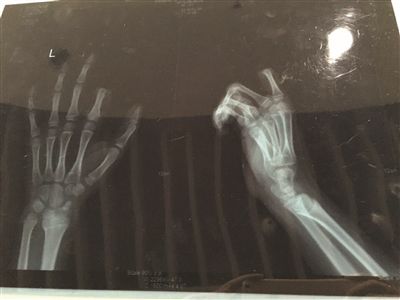

X光片显示孩子食指两个指节被切断。

不一会儿,饭做好了,听见这段对话的邹某,已经对小朋一直玩游戏的状态有些不满,便忍不住对小朋训斥了几句。当时,小朋手里正拿着叉子在叉土豆泥吃,听了爸爸训斥的话后,立马就炸毛了,放下手中的叉子,转身就拿起了身后矮桌上的菜刀,朝着自己的左手切下去,当场,食指的两个指节就掉了下来。

<p>手术历经3个多小时。若能顺利度过一个星期的危险期,接上去的手指便能成活。苏州大学附属瑞华医院手外科主任周荣是小朋的主刀医生。下午1点不到,小朋便被推进手术室做准备,下午4点左右,小朋才被推出了手术室,转入病房。不幸中的万幸,经过三个多小时的手术,小朋的手指被暂时接上。